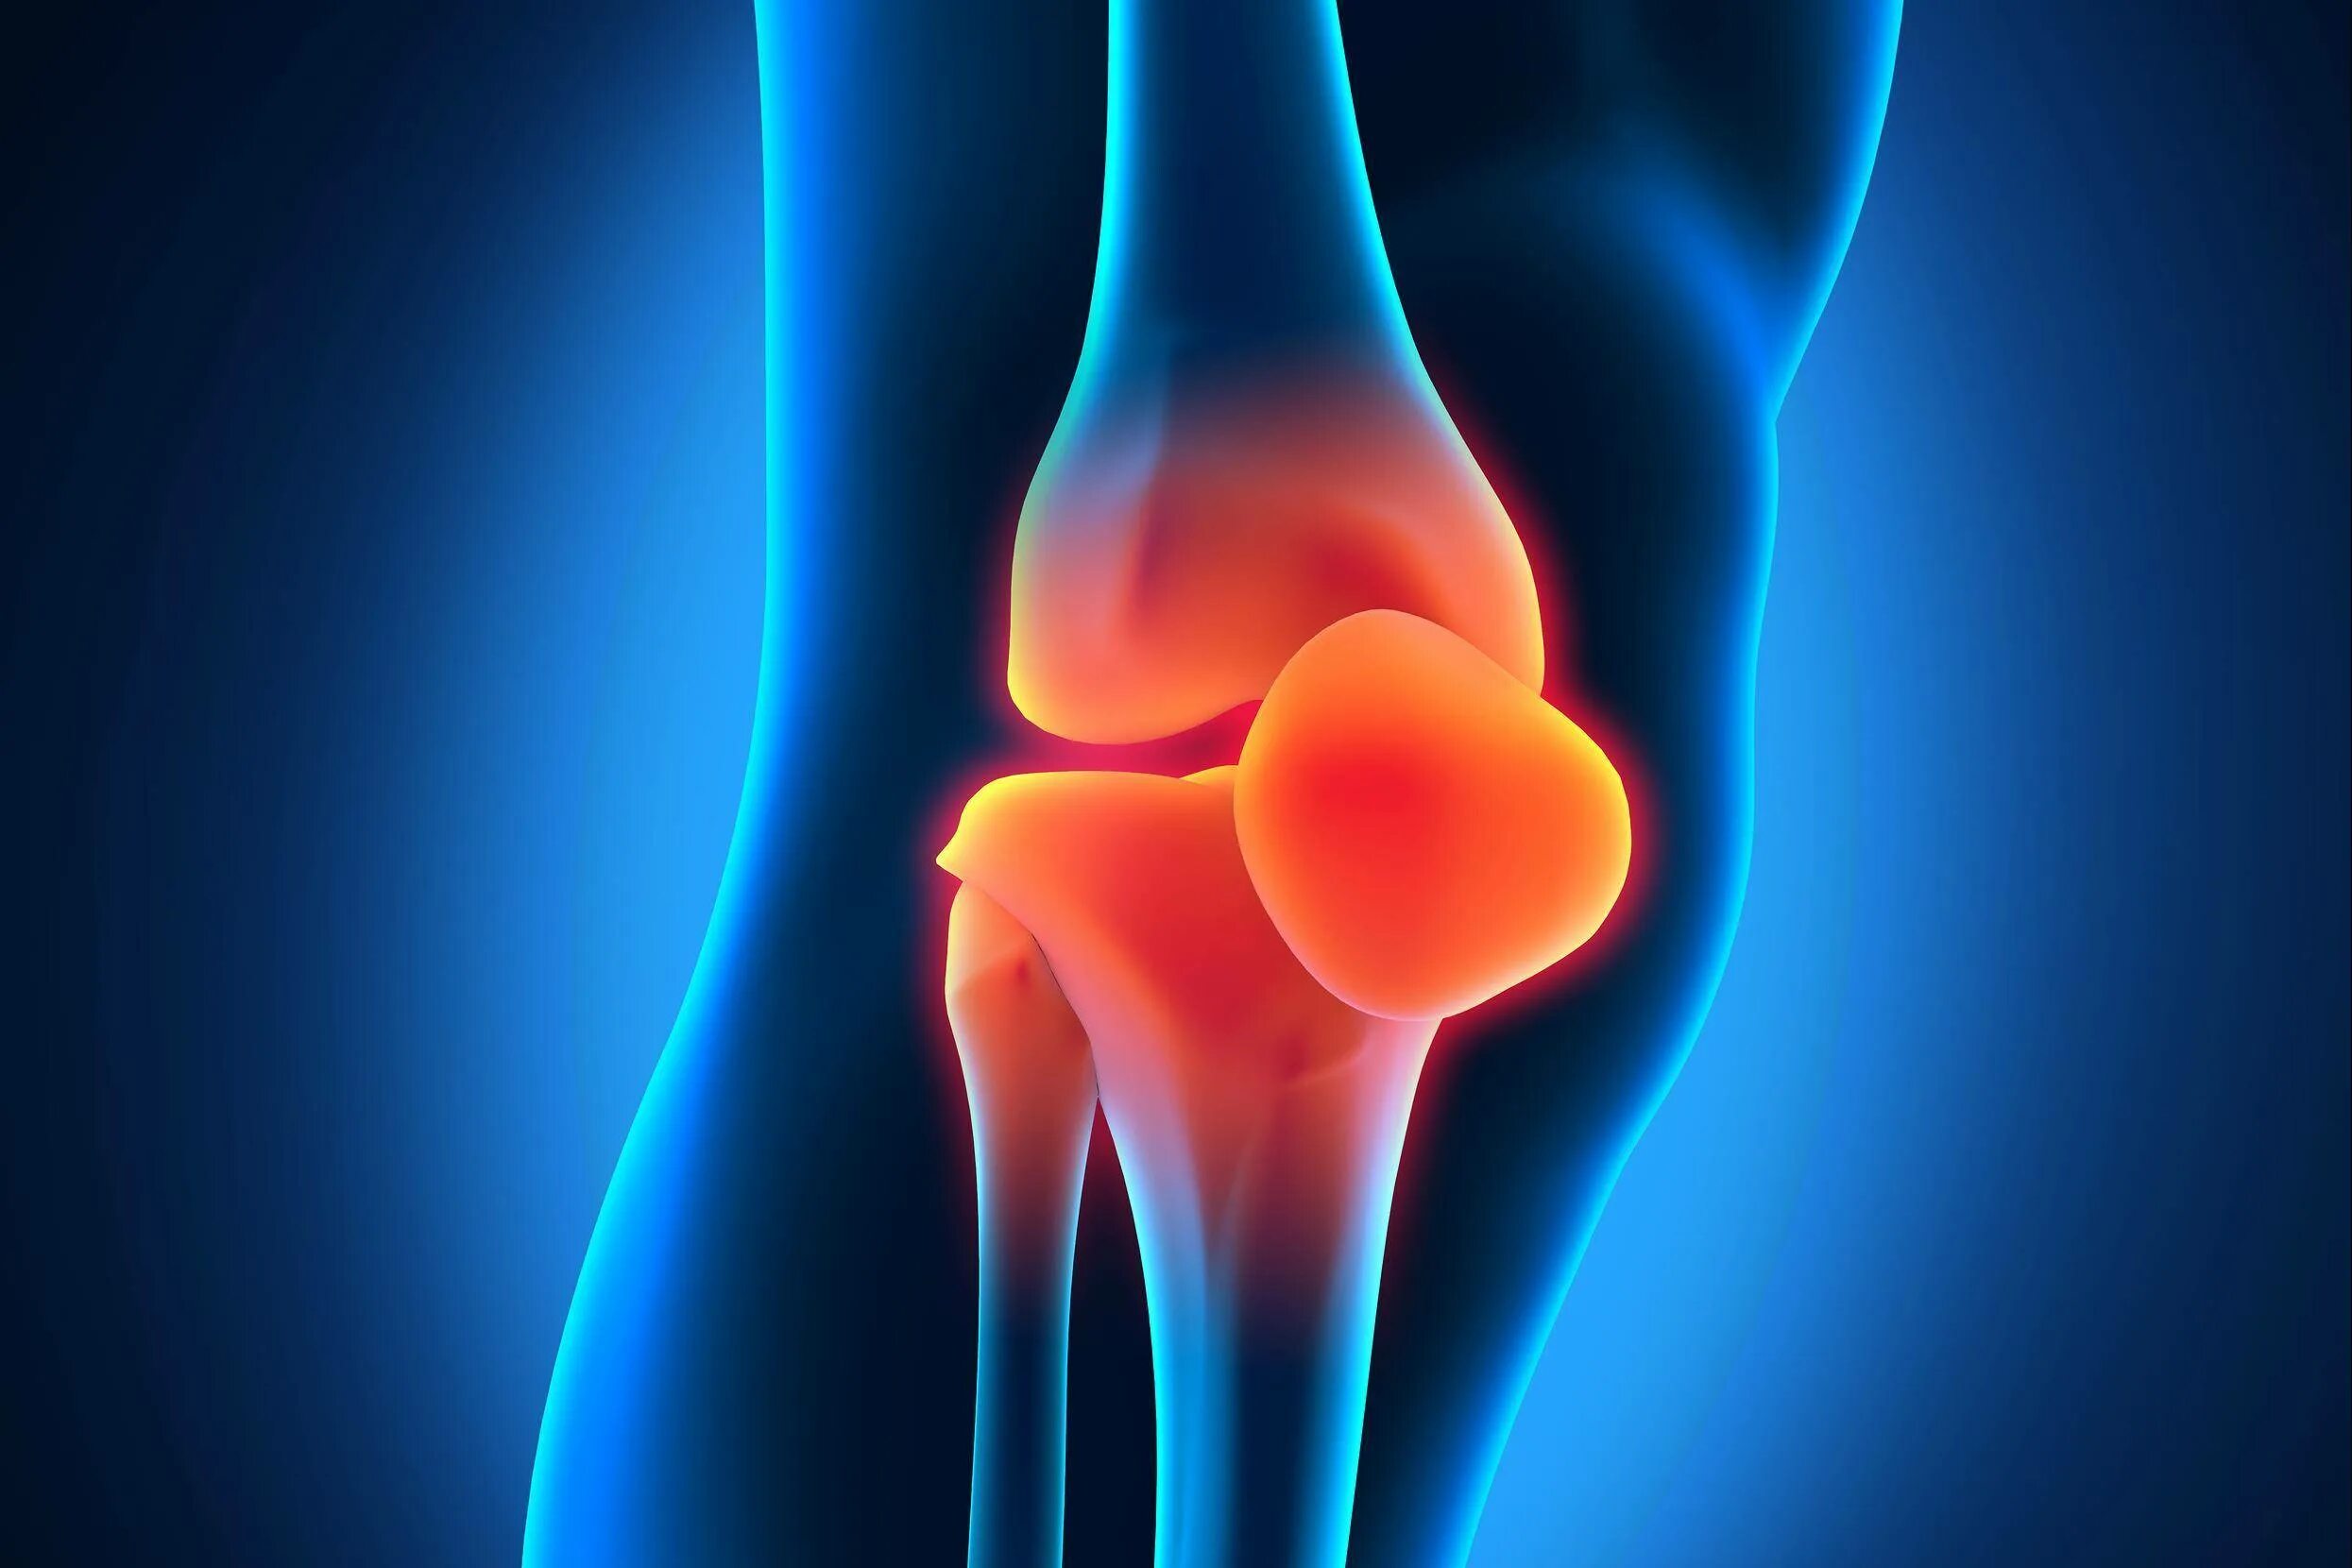

Как лечить синовит тазобедренного сустава